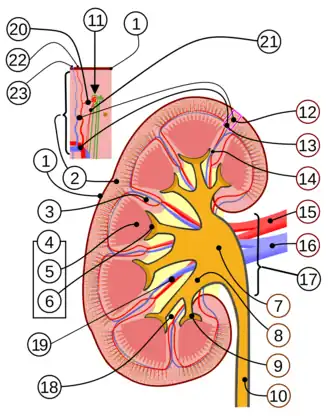

Partes do rim:

1. Cápsula renal 2. Córtex renal 3. Coluna de Bertin 4. Medula renal 5. Pirâmide renal 6. Papila renal 7. Pelve renal 8. Cálice maior 9. Cálice menor 10. Ureter 11. Corpúsculo renal 12. Veia interlobular e Artéria interlobular 13. Veia arqueada e Artéria arqueada 14. Veia interlobar e Artéria interlobar 15. Artéria renal 16. Veia renal 17. Hilo renal 18. Seio renal 19. Veia segmentar e Artéria segmentar 20. Arteríola aferente 21. Arteríola eferente 22. Artéria radial perfurante 23. Veia estrelada | |